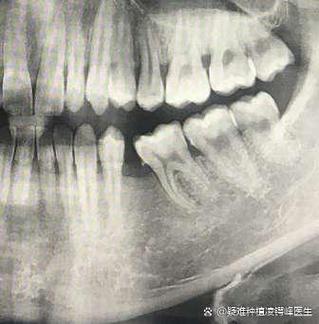

在3月6日的2026赛季中超联赛首轮比赛中,韦林顿·席尔瓦上唇部受伤,赛后第一时间前往华西口腔医院诊治,经检查诊断为:

1.上唇部贯通伤(已清创缝合);

2.第11、21牙半脱位;

3.上颌前牙区牙槽骨骨折。